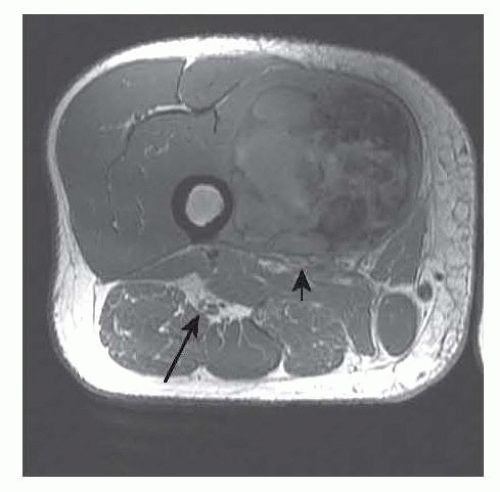

Fat-sensitive images such as T1-weighted sequences are best for identifying critical anatomic structures such as nerves and vessels (FIG 1).

FIG 1 • Axial T1-weighted image demonstrating compartments of the thigh and relevant anatomy of the thigh. The arrow points at the sciatic nerve and the arrowhead at the femoral vessels, and there is a sarcoma in the vastus medialis.